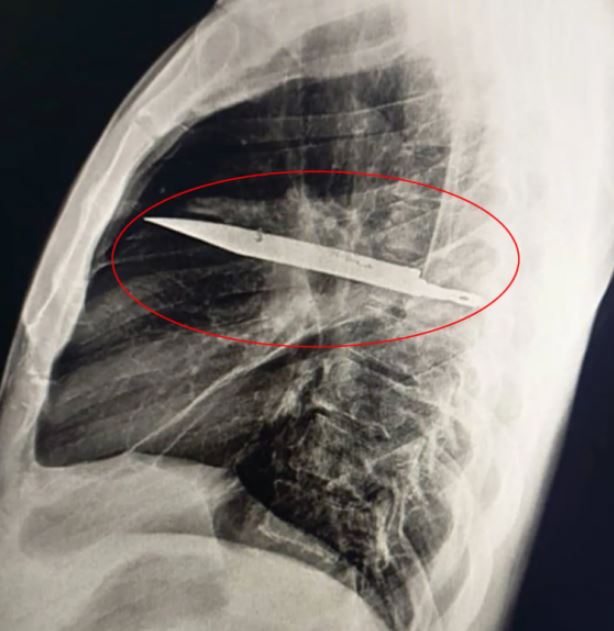

تنزانى يكتشف بالصدفة شفرة سكين دخلت جسمه منذ 8 سنوات بعد ألم فى الصدر السكين تظهر فى الاشاعات

الفحوصات الطبية بالأشعة السينية كشفت المفاجأة المروعة، إذ ظهر جسم معدنى عالق فى منتصف الصدر مع علامات تشير إلى تليف ما بعد الصدمة أو ورم دموى مزمن، وبطريقة غريبة، تمكنت شفرة السكين التى اخترقت لوح الكتف الأيمن من تفادى أى أعضاء حيوية طوال هذه السنوات، وفى وقت الحادثة، لم يكن لدى المستشفى الذى استقبل الرجل وسائل متقدمة لإجراء فحوصات إشعاعية، ومع غياب الألم بعد التئام جروحه، لم يبحث أحد أكثر، وفقا لـ oddity central.